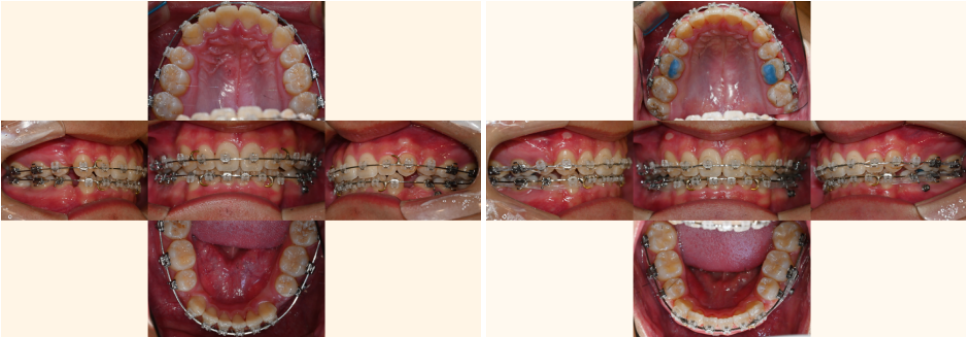

22.08.12

매복된 치아를 끌어내기 위한

공간을 만드는 과정입니다.

첫 번째 작은 어금니를 발치하여

필요한 공간을 확보해요.

이 치아는 저작 기능이 상대적으로 낮고,

발치 후 공간을 닫기에도 유리한 위치에 있습니다.

[매복치 견인]

23.02.25

잇몸을 살짝 절개하여 매복된 치아에

교정 장치를 부착하고,

미니스크류나 기타 고정원을 이용해

서서히 정상 위치로 끌어내는 과정이죠.

23.06.23 // 23.11.25

이 과정에서는

이가 올바른 방향으로 나오도록

정기적인 조정과 관찰이 필수입니다.

[사랑니 이동]

24.05.01

손상된 어금니 대신

건강한 사랑니를 앞쪽으로 이동시켜

어금니 역할을 하도록 하는 과정입니다.

이는 임플란트나 브릿지 없이도

자연치만으로

문제를 해결할 수 있습니다.

24.09.05//25.01.10

동시에 절단연 교합과 정중선 문제도

전체적인 치아 이동 과정에서 같이 개선됩니다.

치아들이 올바른 위치로 이동하면서

자연스럽게 교합 관계도 정상화되죠.